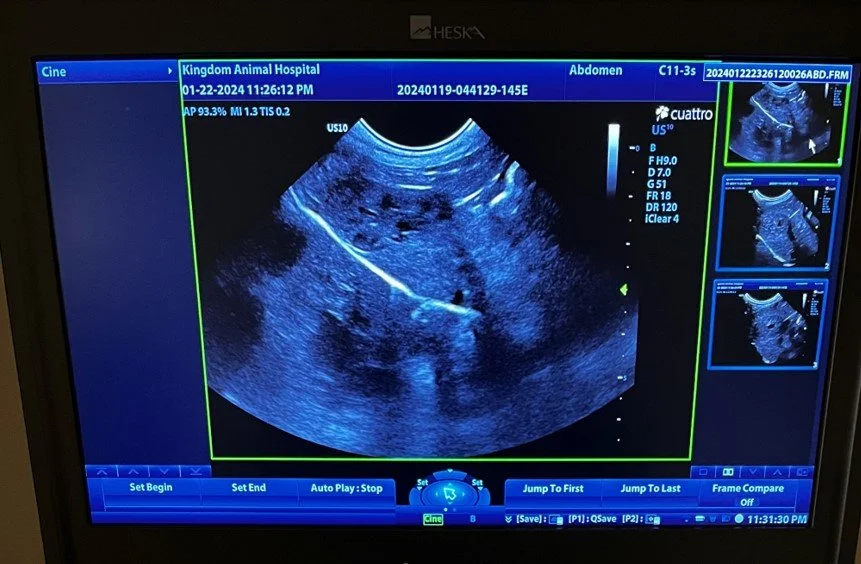

At some point in their life, your dog or cat will need more than preventive health care. Kingdom’s medical team is here to help, with advanced diagnostic and medical care. We will give you confident assurance that with our highly trained medical staff, your pet is in the very best hands possible. We perform diagnostics including bloodwork, radiographs, and ultrasound during your appointment whenever possible, so you can get the answers you need for your sick pet and start the appropriate treatment plan right away.